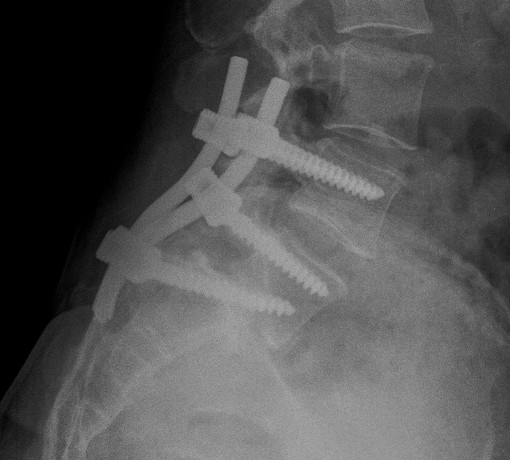

Standing AP and Lateral X-ray

Findings

May miss subtle listhesis on supine XR

- spondylosis

- Meyerding classification

- slip angle

- sacral inclination

Meyerding Classification

Degree of slip compared with width of S1

- Grade I 0-25%

- Grade II 25-50%

- Grade III 50-75%

- Grade IV 75-100%

- Grade V > 100% / Spondyloptosis

Stability

- stable / slip < 50%

- unstable / slip > 50%

Instrumented fusion in situ without reduction

Indications

- slip grade 1 or II

- grade III or IV with no sagittal malalignment

Levels instrumentation

- L5 / S1 grade I or II

- L4 / S1 grade III or IV